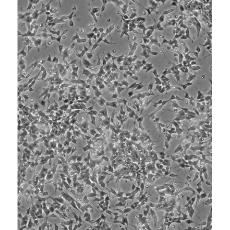

SH-SY5Y [SHSY-5Y]

產(chǎn)品名稱 SH-SY5Y [SHSY-5Y]

中文名稱 人神經(jīng)母細胞瘤細胞

組織來源 神經(jīng)母細胞瘤;骨髓來源;男性

細胞種屬 Homo sapiens, human

生長特性 mixed, adherent and suspension

形態(tài)特征 epithelial-like and neuronal-like

細胞描述 SH-SY5Y cells have a reported saturation density greater than 1×10^6 cells/cm^2. They are reported to exhibit moderate levels of dopamine beta hydroxylase activity. Ref